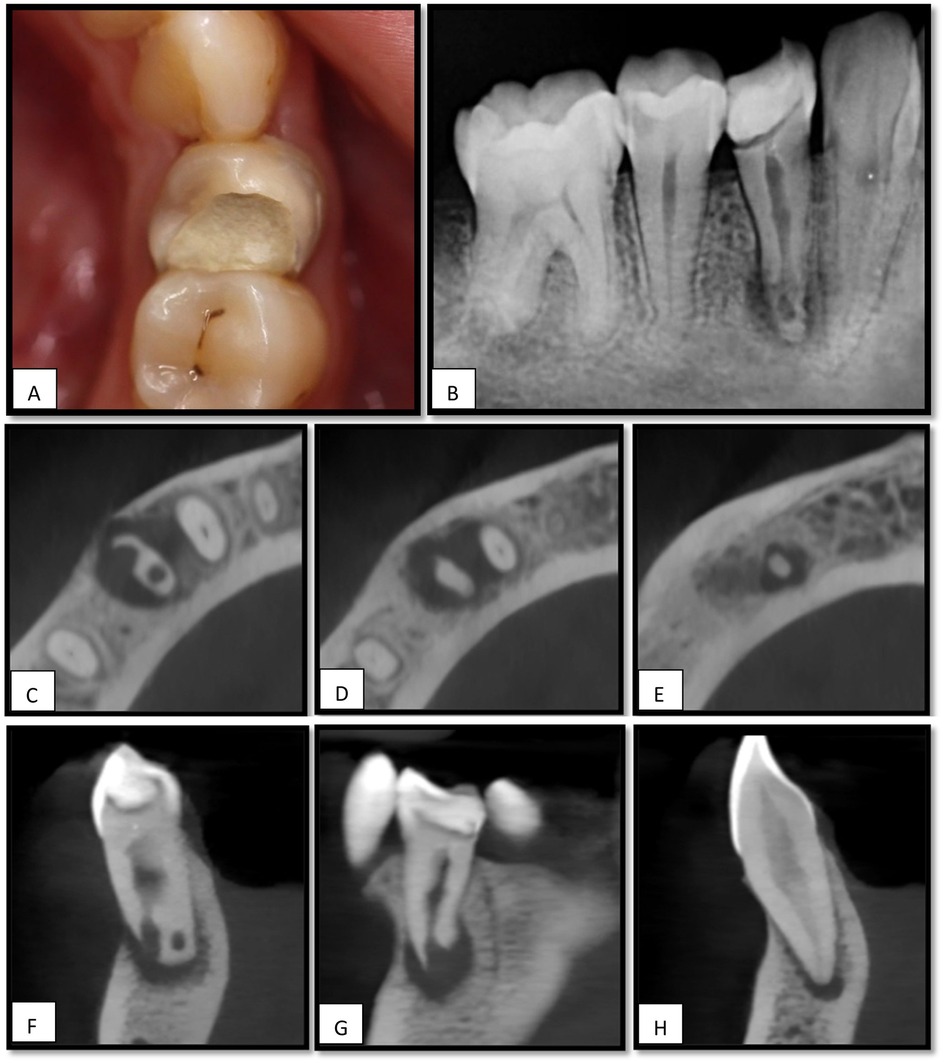

The patient underwent an inferior alveolar nerve block using 2% lidocaine with 1:100,000 epinephrine. Rubber dam isolation was performed, and the temporary restoration was removed. Caries excavation was completed (Figure 2A), after which a Teflon tape was placed over the canal orifice to protect it during coronal build-up with the composite resin. Subsequently, the access cavity was refined (Figure 2B) under magnification using a CJ-Optik Flexion (CJ-Optik, Wetzlar, Germany). Examination revealed a single orifice bifurcating into two distinct canals in the middle third of the root.

Figure 2. (A), Cavity after caries excavation. (B), Access cavity refinement after coronal build-up. (C), Working length determination using size 10 K-file in the lingual canal and size 50 H-file in the buccal canal. (D), MTA apical plug in both canals, (E), Thermoplastic Obturation of the remaining canal space done till the CEJ, (F), PA showing the apical plug with slight extrusion of the material. (G), PA showing the obturation of #44, (H), Composite resin restoration placed.

The working length was determined using an electronic apex locator (EAL) in combination with an intraoral periapical radiograph. A 10 K-file was positioned 17 mm from the lingual canal, whereas a 50 H-file reached 15.5 mm from the buccal canal (Figure 2C).

Canal preparation was performed using the ProTaper Ultimate system, sequentially employing the shaper and F1 and F2 files. Minimal manual instrumentation with 40 H-files was performed for the buccal canal. The final irrigation included 2% sodium hypochlorite (NaOCl) with activation using an ultrasonic device (Irri Safe tip) for three cycles, followed by 5 mL of 17% EDTA for 1 min, and a final rinse with 2% NaOCl.

Calcium hydroxide [Ca(OH)₂] was not employed in this case. The decision was based on the extent of apical root resorption, which required immediate apical sealing with mineral trioxide aggregate (MTA) and subsequent intentional reimplantation, rather than attempting to arrest resorption with intracanal medicaments. Obturation was achieved by placing a mineral trioxide aggregate with conventional setting (ProRoot MTA, Dentsply Sirona, USA) in the apex 6 mm of both canals (Figures 2D,E). A slight accidental extrusion of the material occurred (Figure 2F). The remaining canal spaces were backfilled with thermoplasticized gutta-percha (Figure 2G), and the final composite resin restoration was placed (Figure 2H) and the patient was scheduled for surgical intervention.

2.3 Second visit: surgical day

The patient reported remaining asymptomatic after completion of the single-visit endodontic treatment. At the second visit, 5 days after the RCT, the patient was instructed to rinse with 0.12% chlorhexidine gluconate and received 400 mg of ibuprofen as premedication. Two surgeons performed the procedure. Following standard surgical preparation, profound anesthesia was achieved via an inferior alveolar and lingual nerve block and buccal infiltration using 2% lidocaine with 1:100,000 epinephrine. The mucoperiosteal flap was carefully reflected to expose the apical portion of the crown margin. The tooth was then gently extracted using forceps with contact placed above the cemento-enamel junction (CEJ) to ensure minimal trauma to the surrounding tissues (Figure 3A).

Figure 3. (A), Tooth # 44 extracted using lower premolar forceps, (B), cutting the apical 4 mm by high-speed straight fissure diamond bur, (C), the lingual canal has insufficient MTA filling, (D), preparing the apical 3 mm from the lingual canal by ultrasonic, (E), retrograde filling using MTA pro-root in the lingual canal. (F), Extruded root filling material is curetted. (G), Granulation tissue is removed from the socket. (H), Intraoral view of the extraction socket before reinsertion. (I), Periapical radiograph of an empty socket related to tooth #44. (J), Post-operative clinical view after reimplantation of tooth #44, (K), Periapical x-ray shows the tooth #44 after reimplantation, (L), Tooth is stabilized using flexible splint (orthodontic wire) and composite resin.

Immediately after extraction, the extraoral phase was initiated and timed. The extracted tooth was handled gently with taped forceps and rinsed with sterile saline to remove debris without desiccating or scraping the root surface under magnification using a CJ-Optik Flexion (CJ-Optik, Wetzlar, Germany). The apical third was examined, and a 4 mm apical resection was performed using a high-speed handpiece under copious irrigation to eliminate the area of resorption (Figures 3B,C).

A retrograde cavity, approximately 3 mm in depth, was prepared in the lingual canal using a diamond-coated ultrasonic tip (ED10D; Satelec Acteon, Mérignac, France) (Figure 3D) and filled with TotalFill RRM Fast-Set Putty (FKG Dentaire, Switzerland)to ensure a three-dimensional apical seal (Figure 3E).

While the tooth was undergoing extraoral treatment, the second surgeon gently curetted the apical portion of the extraction socket to remove the extruded material (Figure 3F) and granulation tissue (Figure 3G), taking care not to disturb the socket walls coronal to the apex (Figures 3H,I).

Care was taken to limit the total extra-oral time to less than 10 min. Once the root-end procedure was completed, the tooth was carefully reinserted into the original socket (Figure 3J) to ensure the correct orientation and passive fit. Subsequently, a flexible splint using an orthodontic wire and composite resin was placed to stabilize the tooth and permit physiological mobility during healing (Figures 3K,L).